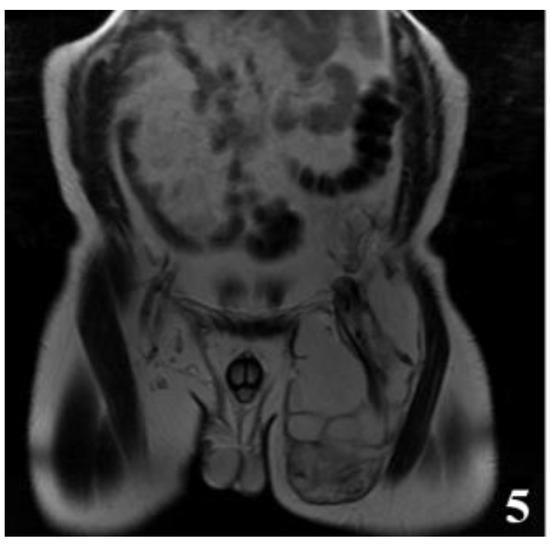

Figure 5.

T2W MRI sequences, coronal—Hydatid cyst of left iliopsoas muscle and left thigh, with daughter cells and Serpent sign present [8] (part 1).